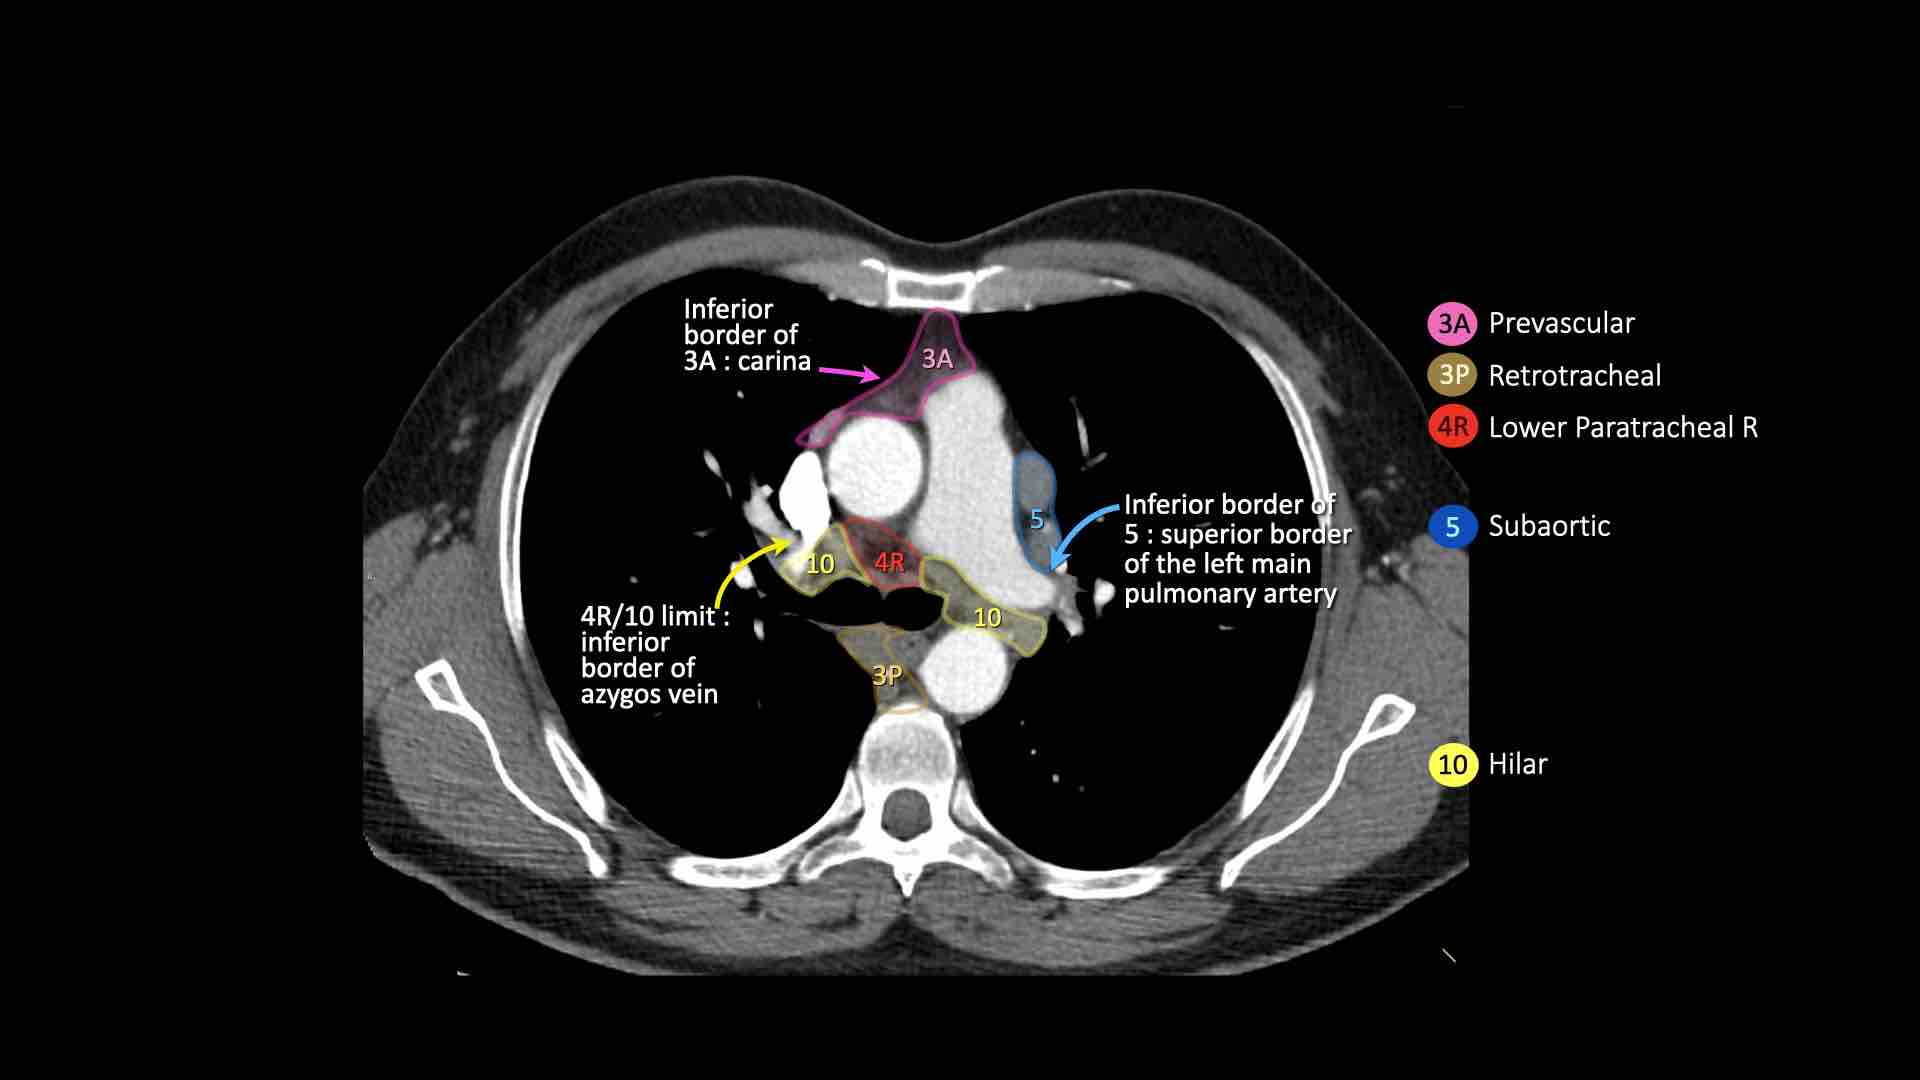

3A.Trước mạch máu

Các hạch này không tiếp giáp với khí quản như các hạch ở nhóm 2, mà nằm ở phía trước các mạch máu.

3P.Trước cột sống

Các hạch không tiếp giáp với khí quản như các hạch ở nhóm 2, mà nằm sau thực quản, tức là ở vị trí trước cột sống.

4R.Cạnh khí quản dưới

Từ điểm giao nhau giữa bờ dưới tĩnh mạch vô danh (tĩnh mạch tay đầu trái) với khí quản đến bờ dưới tĩnh mạch đơn.

Hạch nhóm 4R trải dài từ bờ bên phải đến bờ bên trái của khí quản.

4L.Cạnh khí quản dưới

Từ bờ trên của quai động mạch chủ đến bờ trên của động mạch phổi trái.

5. Dưới động mạch chủ

Các hạch này nằm trong cửa sổ phế động mạch (AP window), ở phía ngoài dây chằng động mạch.

Các hạch này không nằm giữa động mạch chủ và thân động mạch phổi mà nằm ở phía ngoài các mạch máu này.

10. Hạch rốn phổi

Bao gồm các hạch tiếp giáp với phế quản gốc và các mạch máu rốn phổi.

Bên phải, trải dài từ bờ dưới tĩnh mạch đơn đến vùng gian thùy.

Bên trái, từ bờ trên động mạch phổi đến vùng gian thùy.

4R. Hạch cạnh khí quản dưới bên phải

Ranh giới trên: giao điểm của bờ dưới tĩnh mạch vô danh (tĩnh mạch tay đầu trái) với khí quản.

Ranh giới dưới: bờ dưới tĩnh mạch đơn.

Hạch nhóm 4R trải dài đến bờ bên trái của khí quản.

4L. Hạch cạnh khí quản dưới bên trái

Hạch nhóm 4L là các hạch cạnh khí quản dưới nằm bên trái bờ trái của khí quản, giữa đường nằm ngang tiếp tuyến với bờ trên quai động mạch chủ và đường tiếp tuyến với bờ trên động mạch phổi trái.

Nhóm này bao gồm các hạch cạnh khí quản nằm ở phía trong dây chằng động mạch.

Hạch nhóm 5 (cửa sổ phế động mạch) nằm ở phía ngoài dây chằng động mạch.

Bên trái là hình ảnh ở mức phần dưới khí quản, ngay trên carina.

Bên trái khí quản là các hạch 4L.

Lưu ý rằng các hạch 4L này nằm giữa thân động mạch phổi và động mạch chủ, nhưng không nằm trong cửa sổ phế động mạch, vì chúng nằm ở phía trong dây chằng động mạch.

Hạch nằm bên ngoài thân động mạch phổi là hạch nhóm 5.

7. Hạch dưới carina

Các hạch này nằm ở phía dưới carina khí quản, nhưng không liên quan đến phế quản thùy dưới hoặc các động mạch trong phổi.

Bên phải, chúng trải dài xuống đến bờ dưới phế quản trung gian.

Bên trái, chúng trải dài xuống đến bờ trên phế quản thùy dưới.